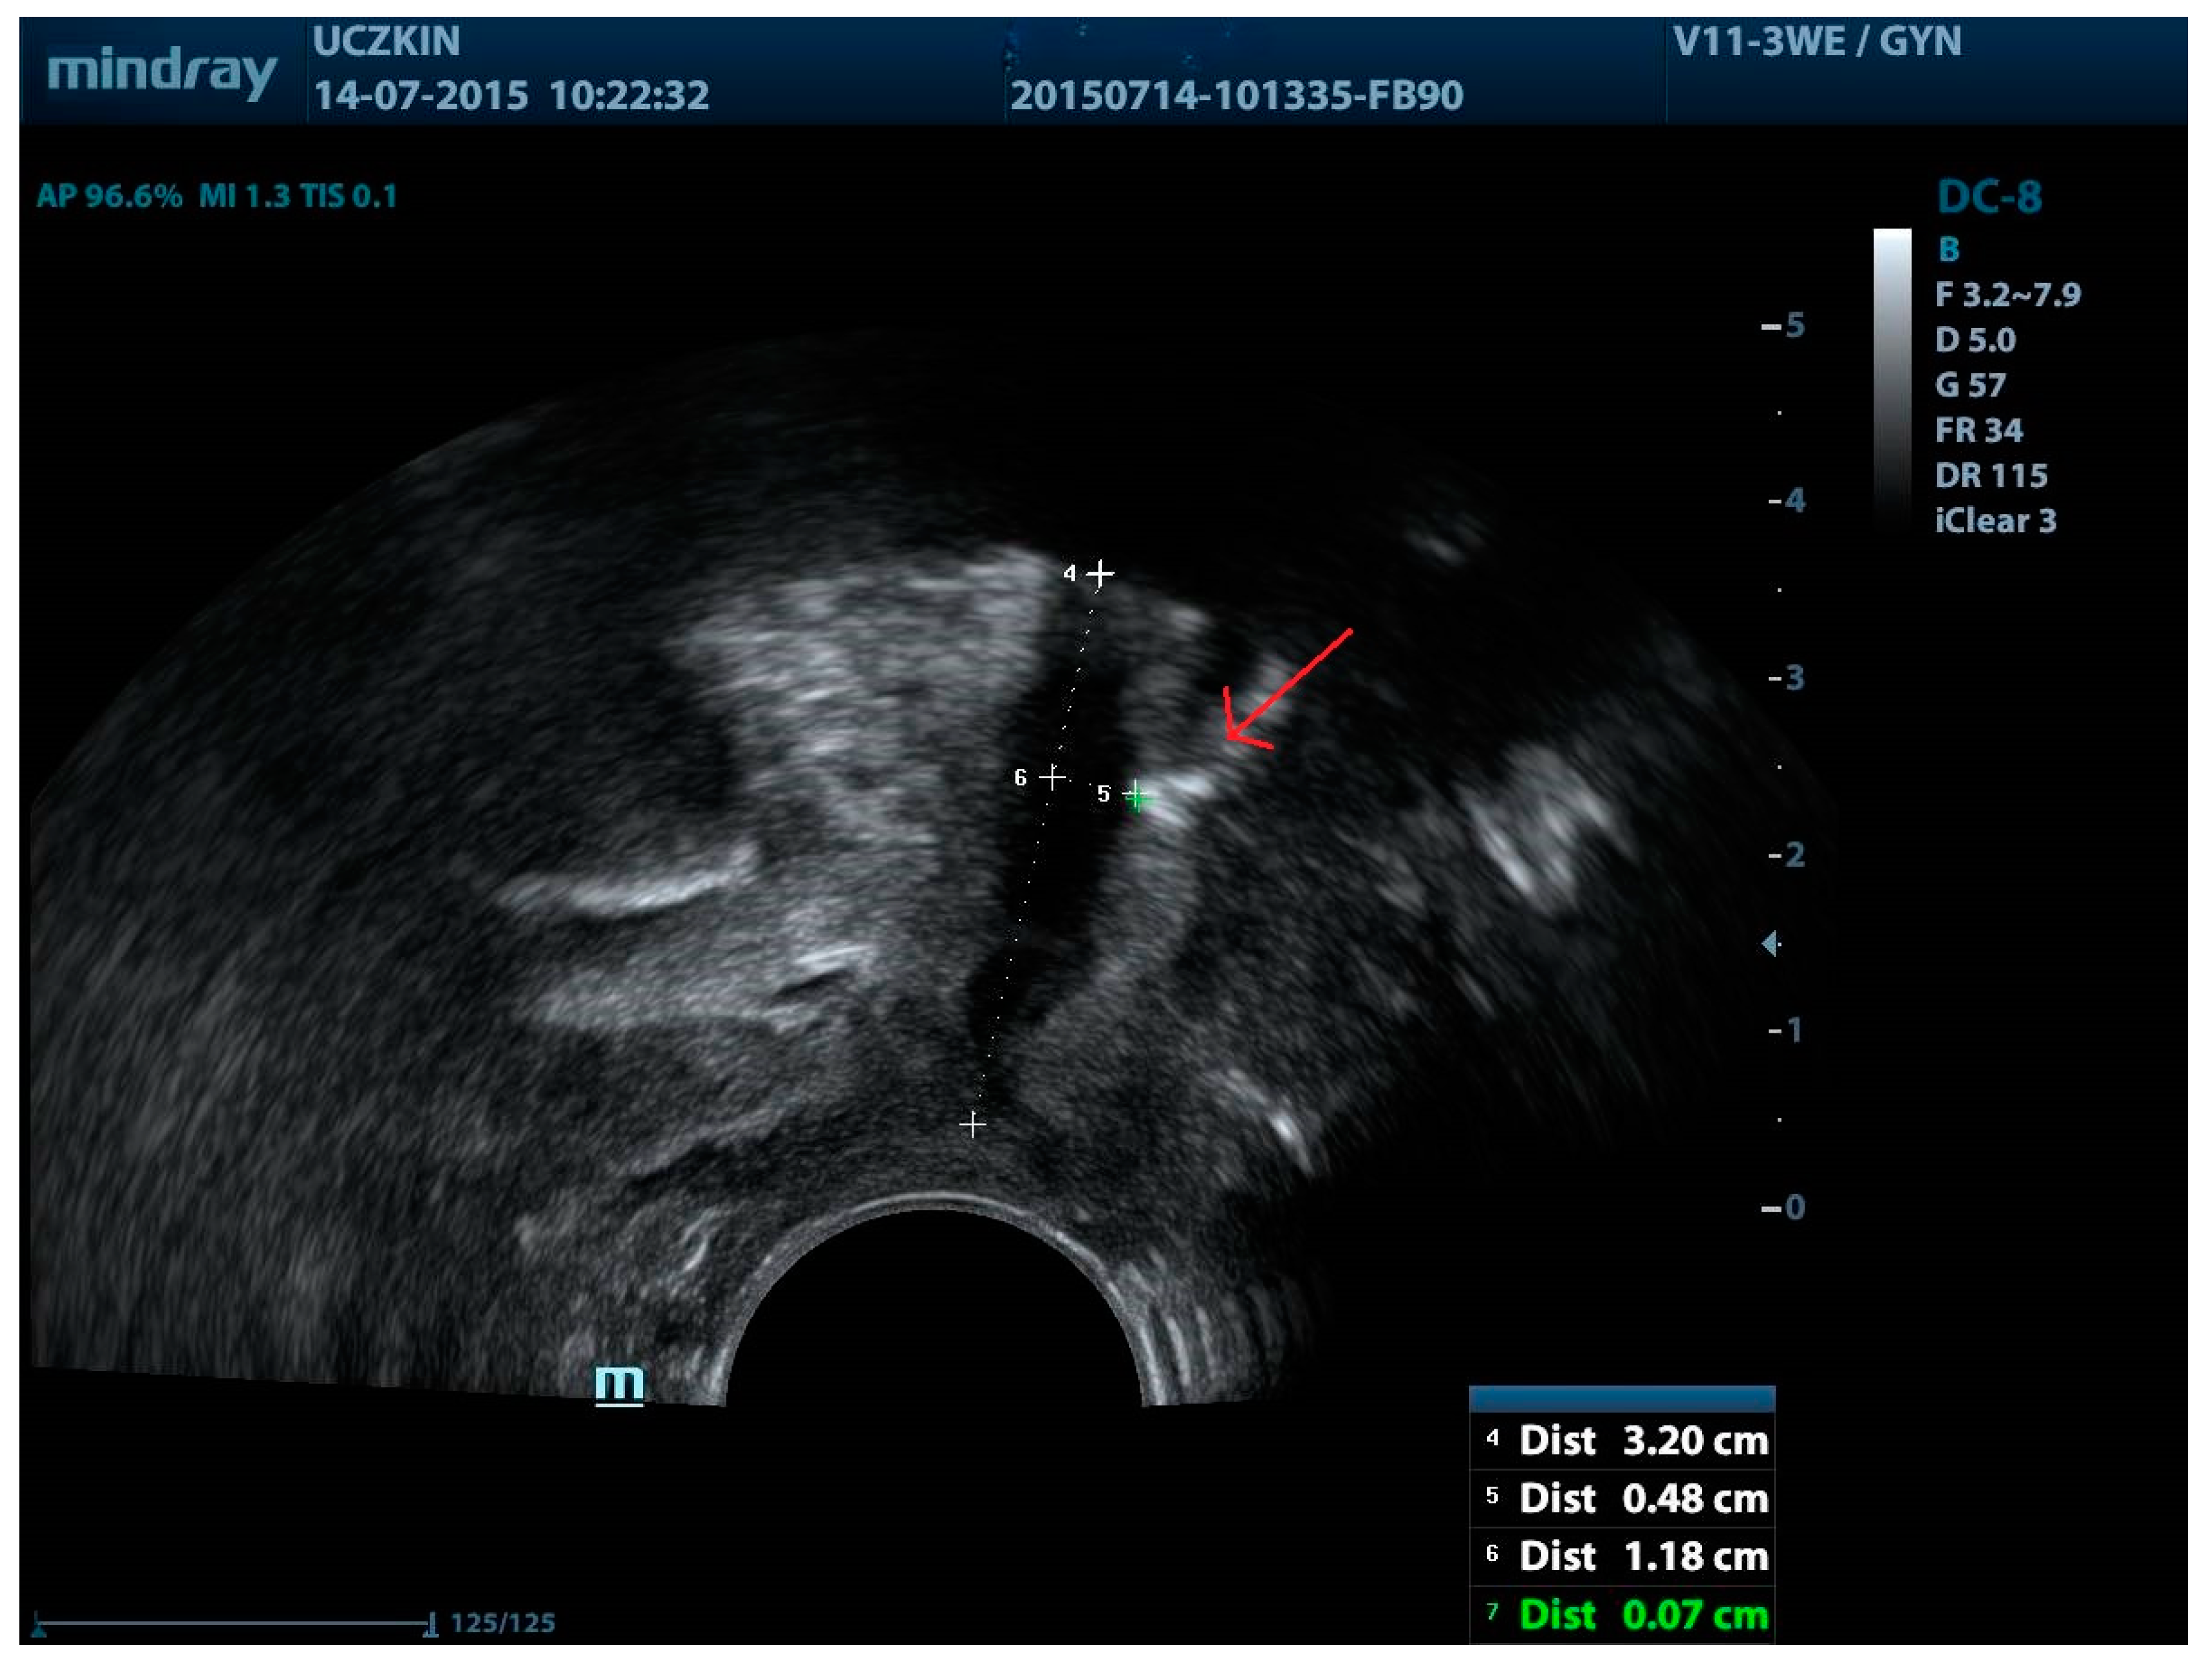

| Urinary Retention and obstructive voiding | Kociszewski et al., 2017 [35] | Median sling-LSM distance = 1.1 mm in the affected patients. |

| Reich et al., 2009 [67] | Tape-urethra distance < 2 mm in the affected patients. | |

| Viereck et al., 2013 [68] | Median sling-SLM distance = 1.5 mm. | |